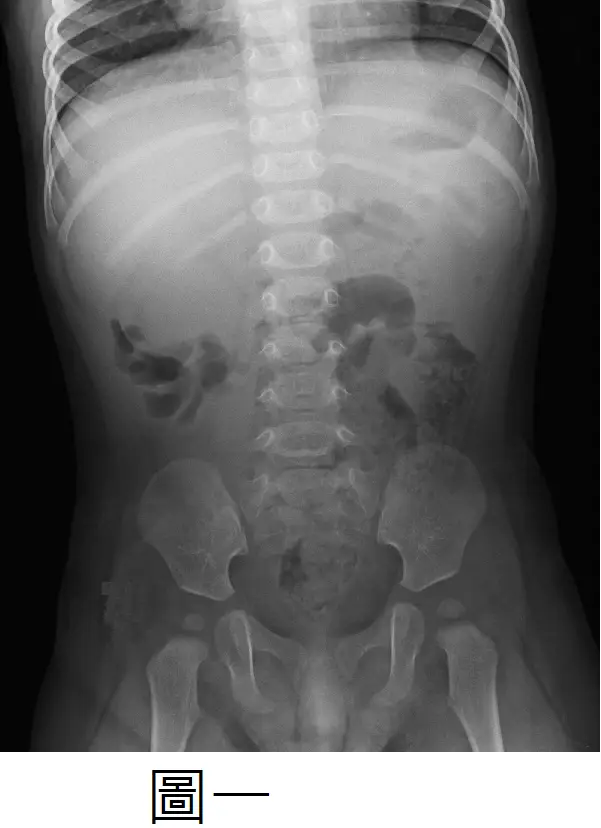

9個月大男嬰發生一陣陣無法安撫的哭鬧,時間持續 3 小時,有嘔吐 3 次,但沒有發燒和腹瀉症狀。腹部 X 光(圖一)和腹部超音波(圖二),最有可能的診斷為何?

圖一(腹部X光)

- 可見右下腹氣體明顯減少(paucity of gas in RLQ),並在右上腹區域隱約呈現一個軟組織密度陰影。

- 此陰影邊緣與腸道遠端氣體形成「新月徵象」(crescent sign),代表迴腸套入升結腸時,其前緣被結腸內氣體勾勒出弧形空隙(radiologykey.com)。

- 同時可注意到近端小腸輕度擴張,支持部分小腸阻塞的現象。